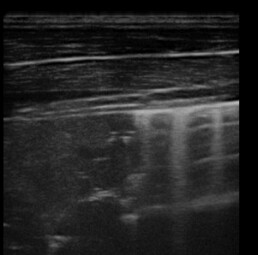

Weiterführende Untersuchungen: Sonographie

- wir stellten "Kometschweifartefakte" fest, die uns einen Hinweis auf zelluläre Infiltration liefern

- Kontrolluntersuchung der entsprechenden Stellen mit Ultraschall